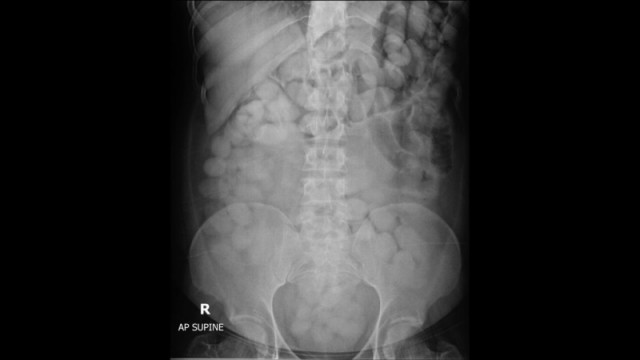

23-летняя Евгения прилетела из Стамбула во Внуково и почему-то попала под подозрение сотрудников таможни. Рентген показал, что внутри Евгении целая куча каких-то свёртков.

Пассажирку задержали и увезли в больницу. Следующие два дня походы Евгении в туалет тщательно контролировала полиция. Вскоре такой надзор дал результат.

Помимо прочего, оказалось, что в девушке поместились 90 чёрных свертков с неизвестным веществом. Их отправили на экспертизу и та показала, что в Евгении путешествовало аж 446 грамм кокаина — теперь по делу о контрабанде ей грозит до двадцати лет.